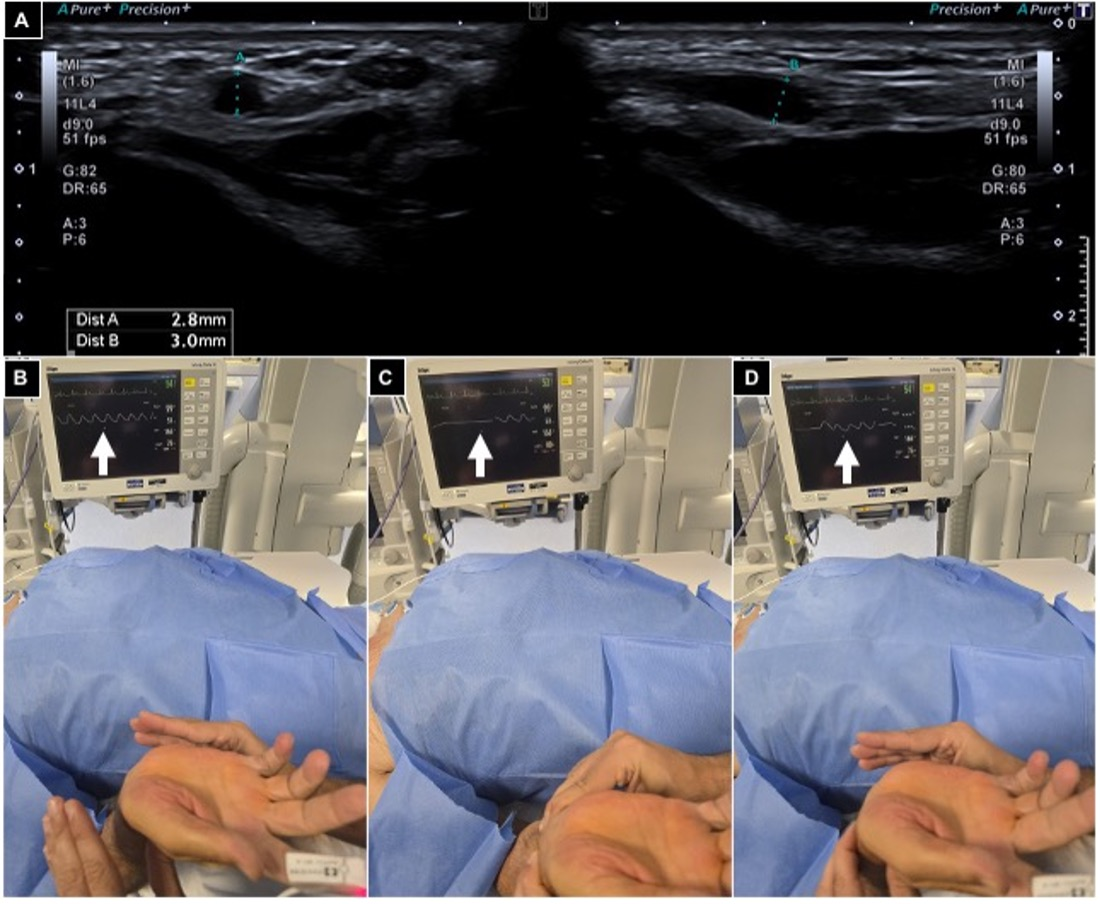

The Barbeau test was conducted by positioning a pulse oximeter on the patient’s index finger; type A-B-C findings were considered suitable for radial access (Figure 2).

Figure 2.

Pre-procedural radial artery evaluation. (A) Arterial caliper evaluation using US out of plane and in plane, showing a value > 2 mm; (B–D) Barbeau test positioning an oxygen saturimeter sensor on the right index finger and monitoring waveform variations (white arrows), free flow (B), compressing radial and ulnar arteries (C) and releasing ulnar pressure (D), and detecting a type A wave.